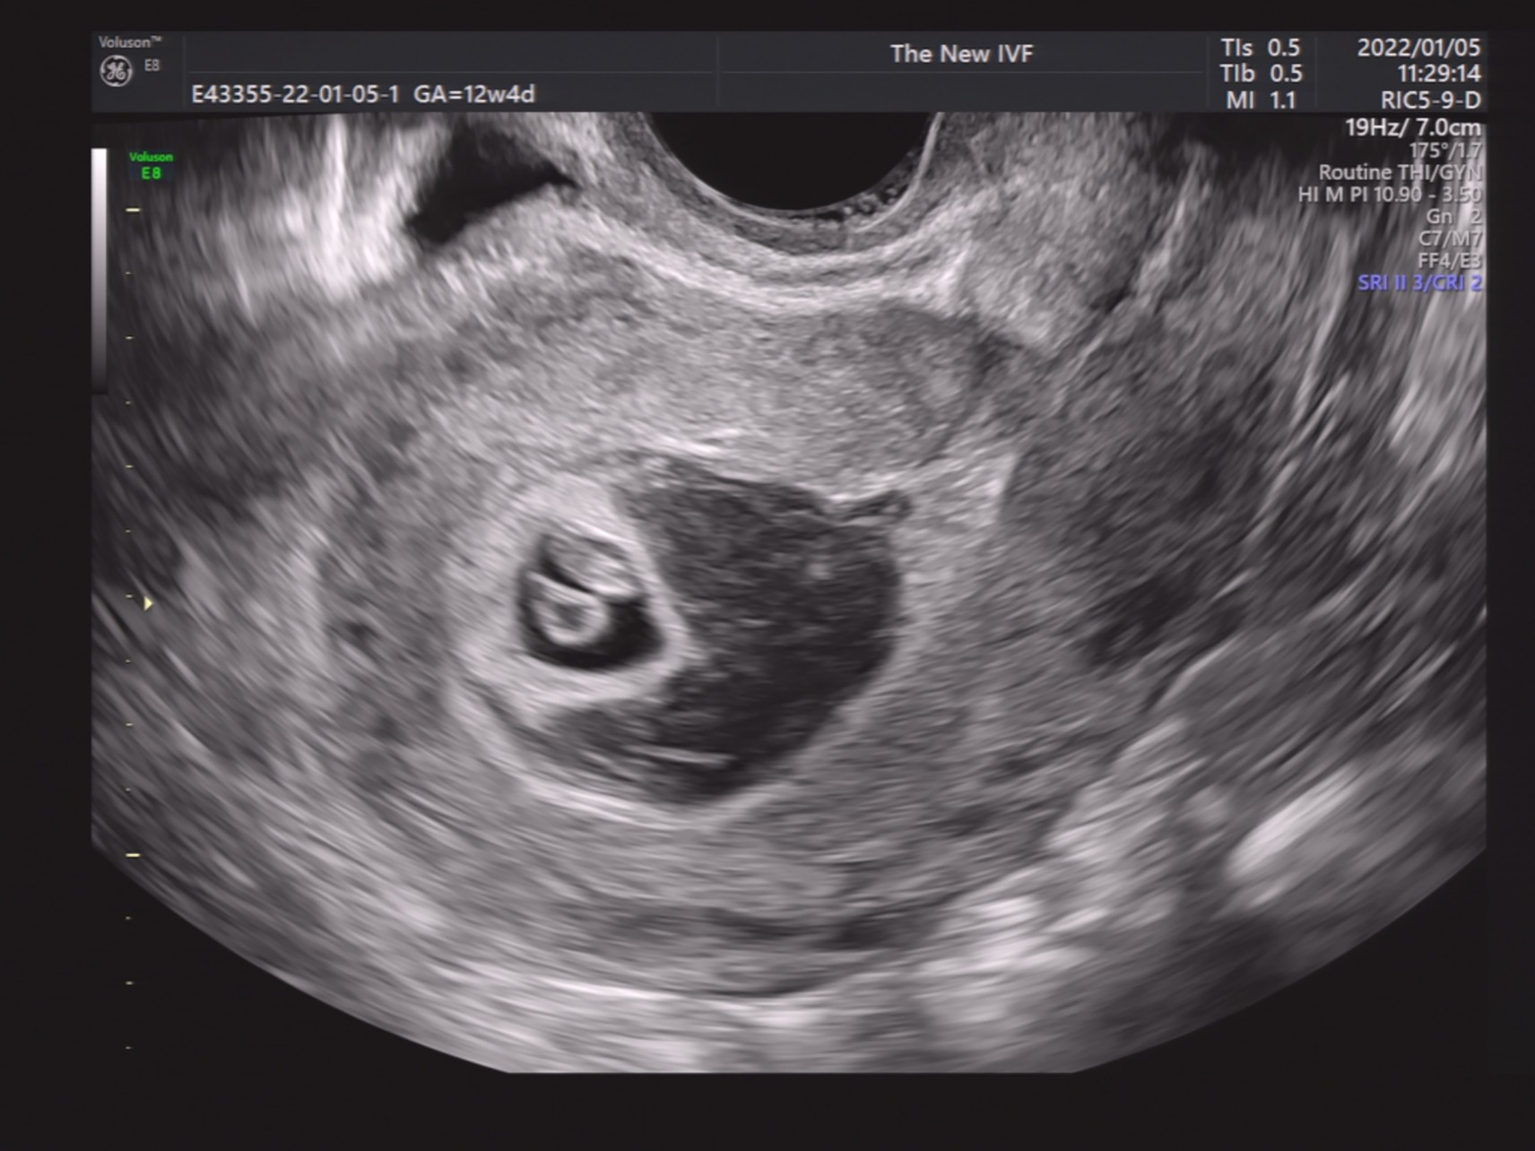

We then performed a subgroup analysis of SCH patients with single GS. Patients were divided into four groups according to the SCH’s proportion in the GS. As shown in Figures 2–5, Figure 2 shows a patient with an SCH whose proportion was less than 50% of the GS; Figure 3 shows that SCH’s proportion was between 50 and 100% of the GS; Figure 4 show that SCH’s proportion was between 100 and 500% of the GS; and Figure 5 shows that SCH’s proportion was larger than 500% of the GS. A significant association was observed between SCH’s proportion in the GS and the miscarriage rate. A larger proportion was associated with a higher miscarriage rate (p for trend: 0.003). The results are shown in Table 5.

Figure 2

A patient with an SCH whose proportion was less than 50% of the GS.